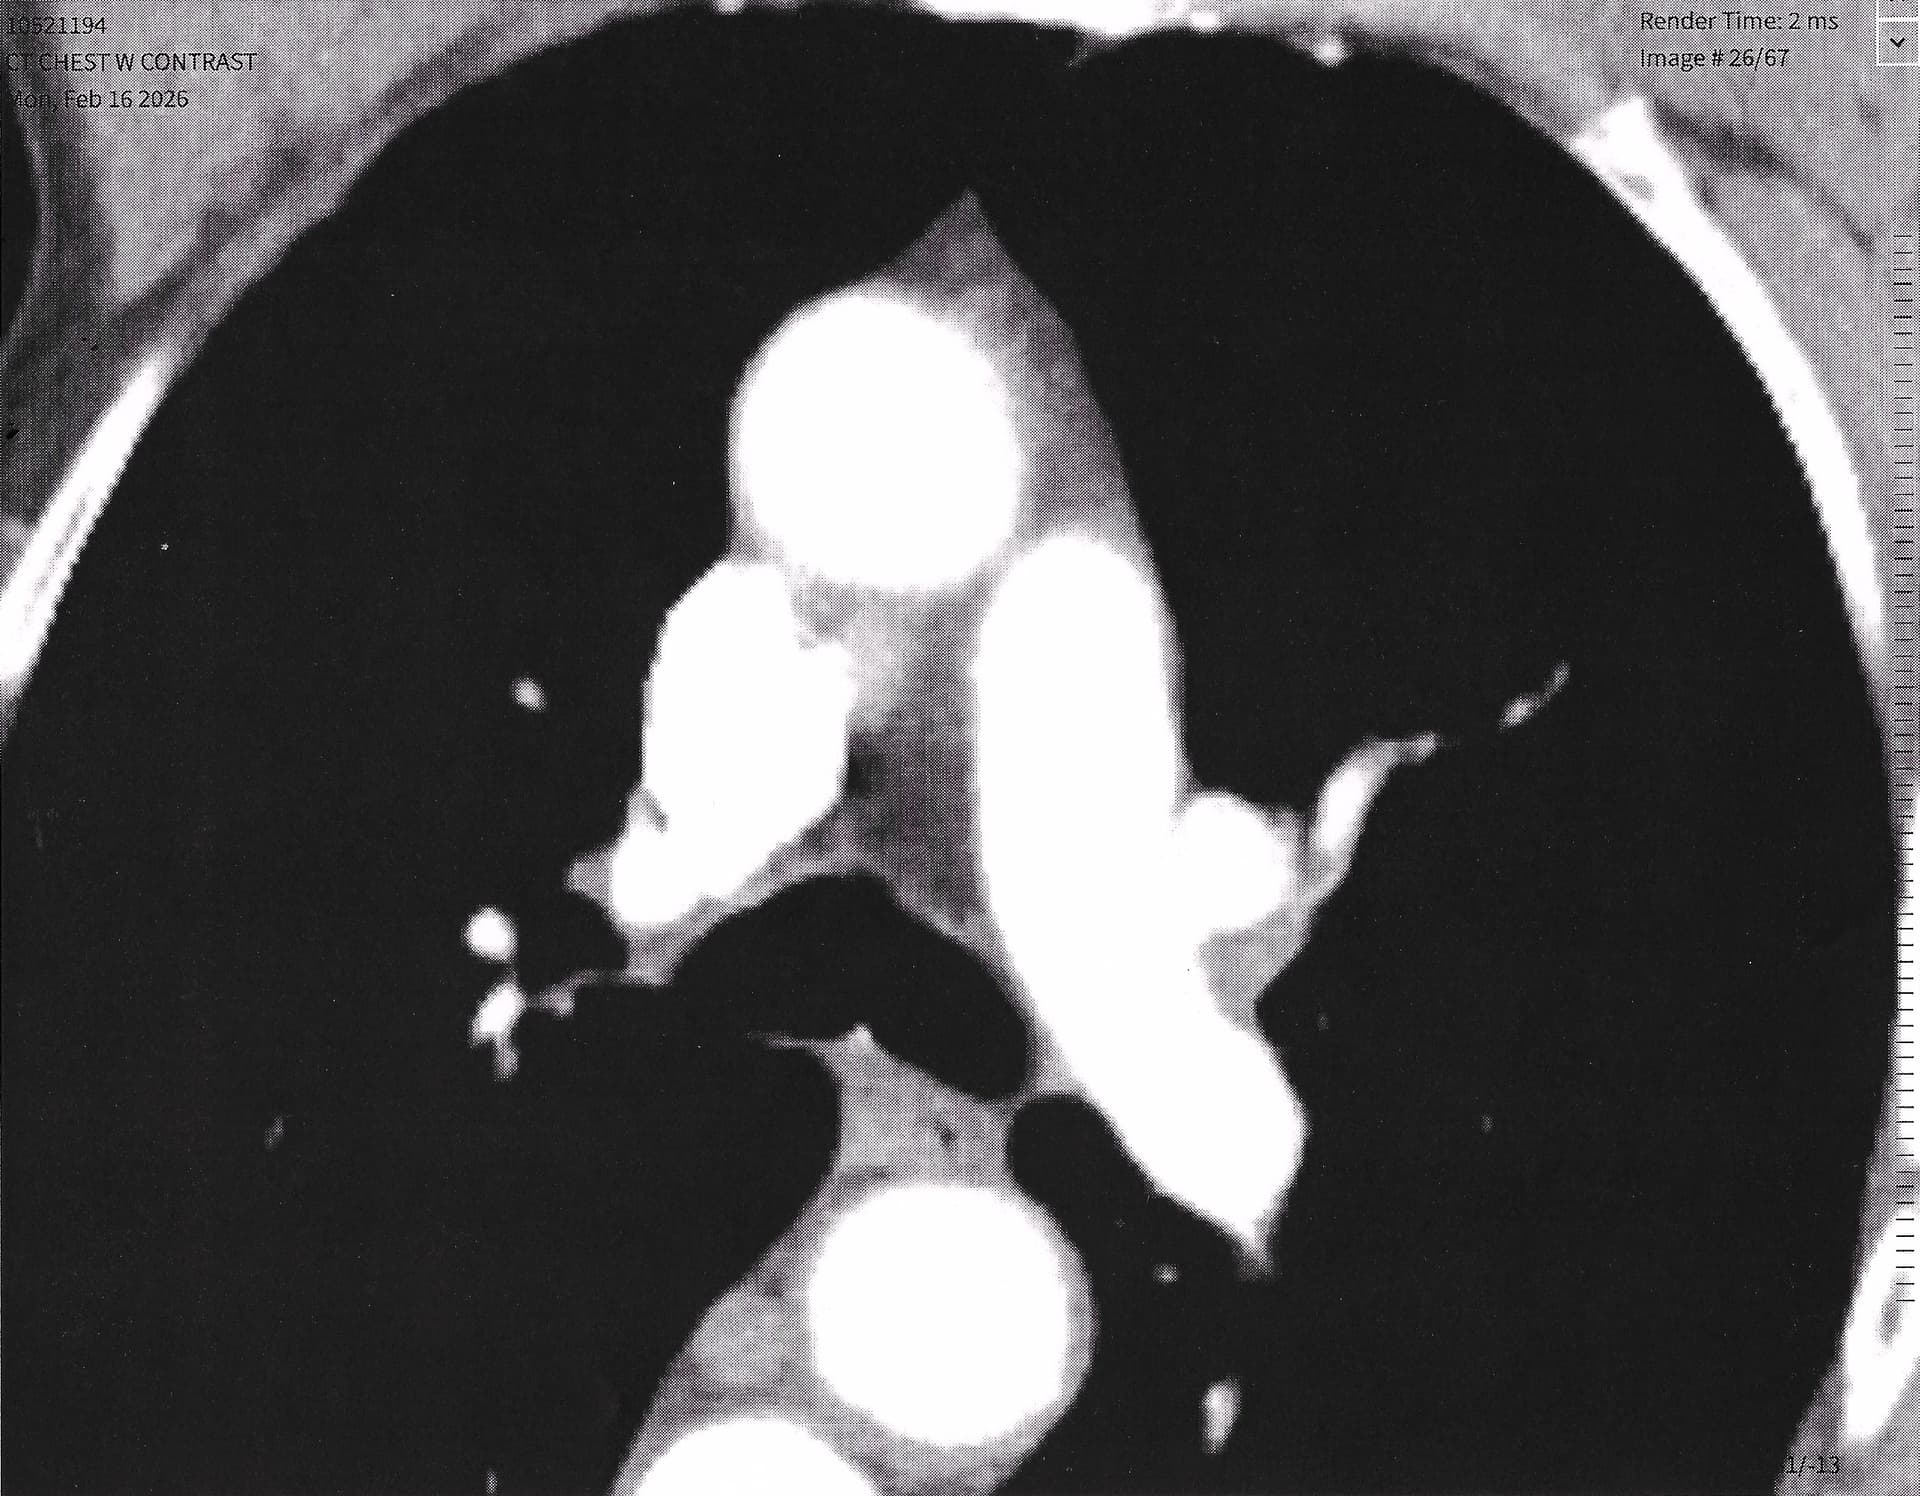

Use the above image as a reference – I did not outline my thymus - it shape is pretty obvious.Click to increase size and detals. Excellent scan.

And now my thymus at the top - pic 25/67 and one layer down - cutting through it… pic 26/67 - it is big, full and fat free.